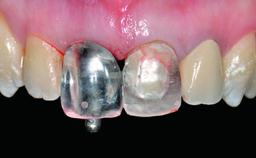

A 36-year-old male patient with a compromised maxillary central incisor was referred by his general dentist for consultation. The patient’s chief complaints were the gradual debonding of a temporary crown on the right central incisor and unsatisfactory esthetics due to an increasing diastema between the right central and lateral incisors. The patient reported a traumatic event some years previously, when a crown had been placed after root-canal treatment. The referring dentist wanted to provide a new crown restoration, but was concerned about the condition of the residual root. Anamnesis was negative for any other dental or periodontal pathology in the remaining dentition. The patient reported taking no medications: He was a smoker (10 to 15 cigs/day) and had realistic esthetic expectations.